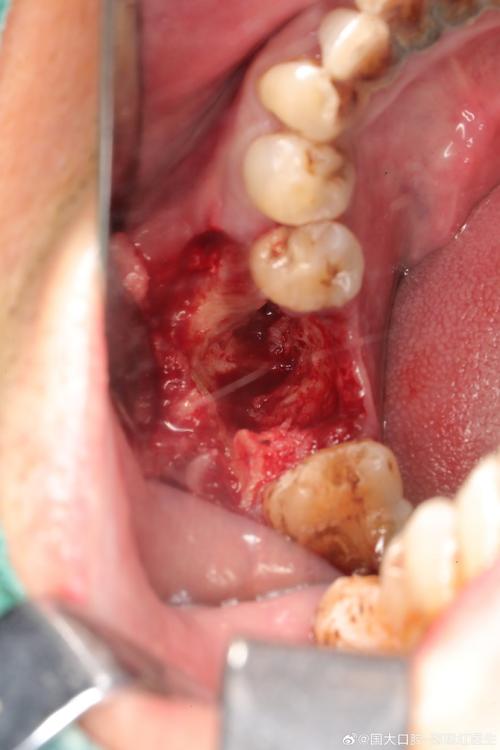

- 视诊:观察牙龈颜色、形态、肿胀、增生、退缩情况。

- 探诊:用牙周探针测量牙龈沟深度、是否有出血、溢脓、种植体松动度,探诊出血是炎症的重要指标。

- 拍X光片:评估牙槽骨状况(是否有骨吸收),检查种植体位置、基台和牙冠的密合度。